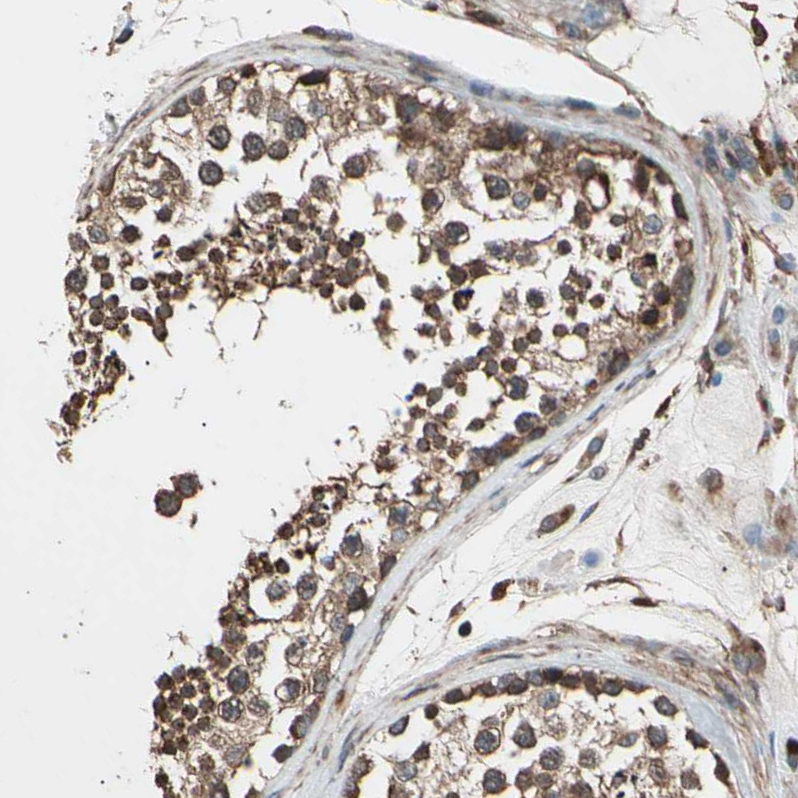

Immunohistochemical staining of human testis shows moderate cytoplasmic positivity in cells in seminiferous ducts.